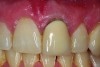

Fig 11. Preoperative photograph.

Figure 11